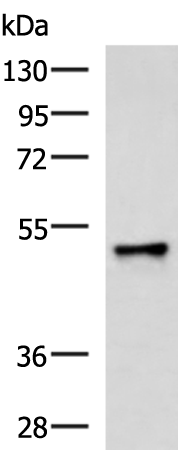

分类: 科研抗体货号: P07403别名: HK2, HCK1, PCN1, ATFB7, HPCN1, KV1.5应用: WB反应种属: Human, Mouse, Rat